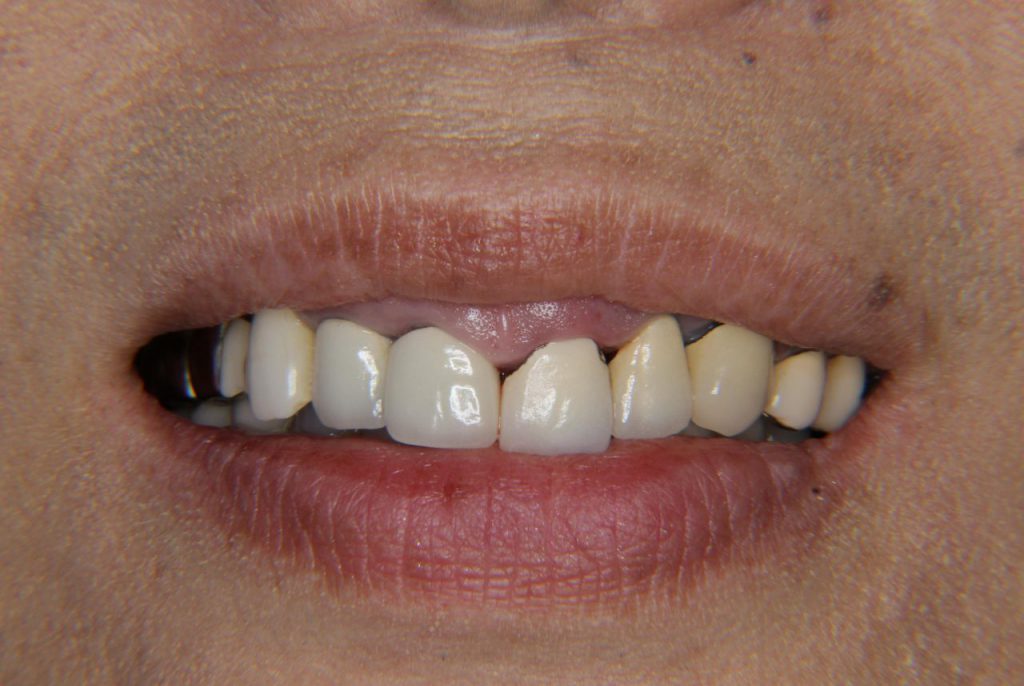

ガミースマイルを歯肉整形手術で改善した症例

ビフォー・アフター、デジタルモックアップ、術後のプロビジョナルレストレーションを紹介しています。外科手術は保険診療、セラミックは自由診療で治療した症例です。